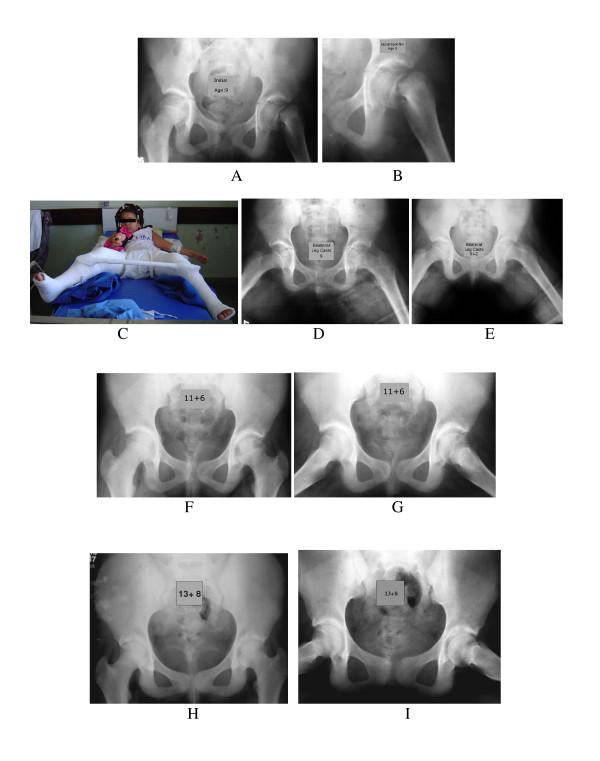

METHODS

The research was performed based on the study of the following variables: symptomatology, and the degree of slipping. A hip spica cast and bilateral short/long leg casts in abduction, internal rotation with anti-rotational bars were used for immobilizing the patient's hip for twelve weeks. Statistical analysis was accomplished by Wilcoxon's marked position test and by the Fisher accuracy test at a 5% level.

A satisfactory result was obtained in the acute group, 70.5%; 94%; in the chronic group (chronic + acute on chronic). Regarding the degree of the slipping, a satisfactory result was obtained in 90.5% of hips tested with a mild slip; in 76% with moderate slip and 73% in the severe slip. The statistical result revealed that a significant improvement was found for flexion (p = 0.0001), abduction (p = 0.0001), internal rotation (p = 0.0001) and external rotation (p = 0.02). Chondrolysis was present in 11.3% of the hips tested. One case of pseudoarthrosis with aseptic capital necrosis was presented. There was no significant variation between age and chondrolysis (p = 1.00).Significant variation between gender/non-white patients versus chondrolysis (p = 0.031) and (p = 0.037), respectively was verified. No causal association between plaster cast and chondrolysis was observed (p = 0.60). In regard to the symptomatology group and the slip degree versus chondrolysis, the p value was not statistically significant in both analyses, p = 0.61 and p = 0.085 respectively.

CONCLUSIONS

After analyzing the nonoperative treatment of slipped capital femoral epiphysis and chondrolysis, we conclude that employment of the treatment revealed that the method was functional, efficient, valid, and reproducible; it also can be used as an alternative therapeutic procedure regarding to this specific disease.